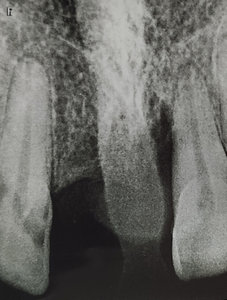

Добрый день. Мне в стоматологии сделали снимок зуба и сказали, что зуб надо удалять, так как вылечить не получится. Подскажите, так ли это? Может стоит обратиться к другим врачам? (фото зуба выслала на e-mail). Зуб № 46. На данный момент зуб не беспокоит. Три месяца назад был флюс, после разреза всё прошло. Антибиотиками не лечила, так как беременность. Сейчас срок 17 недель. Спасибо!

Да, к сожалению зуб необходимо удалить, так как на верхушках всех корней наблюдается обширное воспаление.